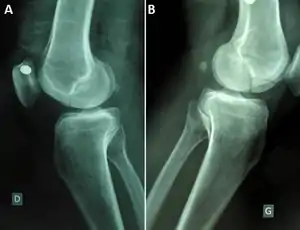

| Medio-lateralradiographsof knees joint showing a bilateral Hoffa fracture of the medial femoral condyle and fracture suspicion of left tibia plateau. (A) right knee; (B) left knee.[1] |